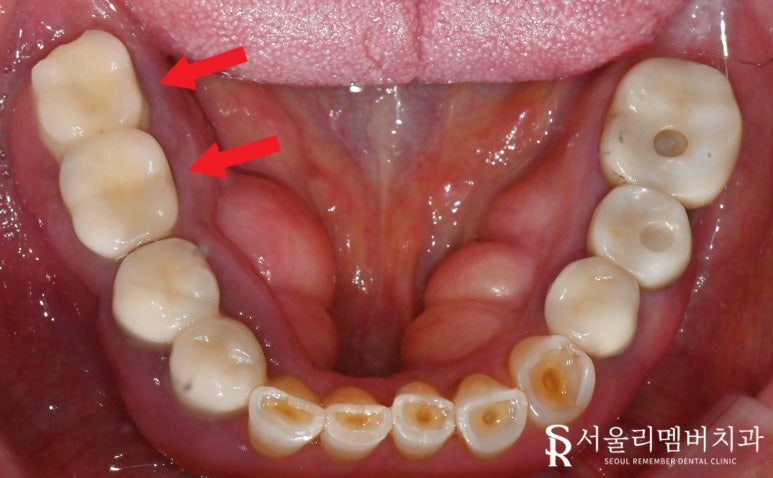

오늘 사당역 치과 에서 보여드리는 케이스를 보면

오른쪽 아래 두 개의 큰 어금니에

임플란트 브릿지 보철이 수복되어 있는데

자세히 보면 해당 부위 주변 잇몸이 부어있고

조금만 건드려도 출혈이 발생하는 상황이었습니다.

염증이 잔뜩 차오르면서

매우 적은 자극에도 반응을 일으키는 것인데요,

겉은 보철로 덮여있으니

정확한 내부 상태 파악을 위해

엑스레이를 찍어보았습니다.

사당역 치과 에서

최종 보철을 올린 모습을 보며

한 가지 더 설명드리겠습니다.

교합면에 작은 홀(hole)이

뚫려있는 게 보이시나요?

이것은 SCRP type에 해당하며

의도적으로 만들어둔 것인데요,